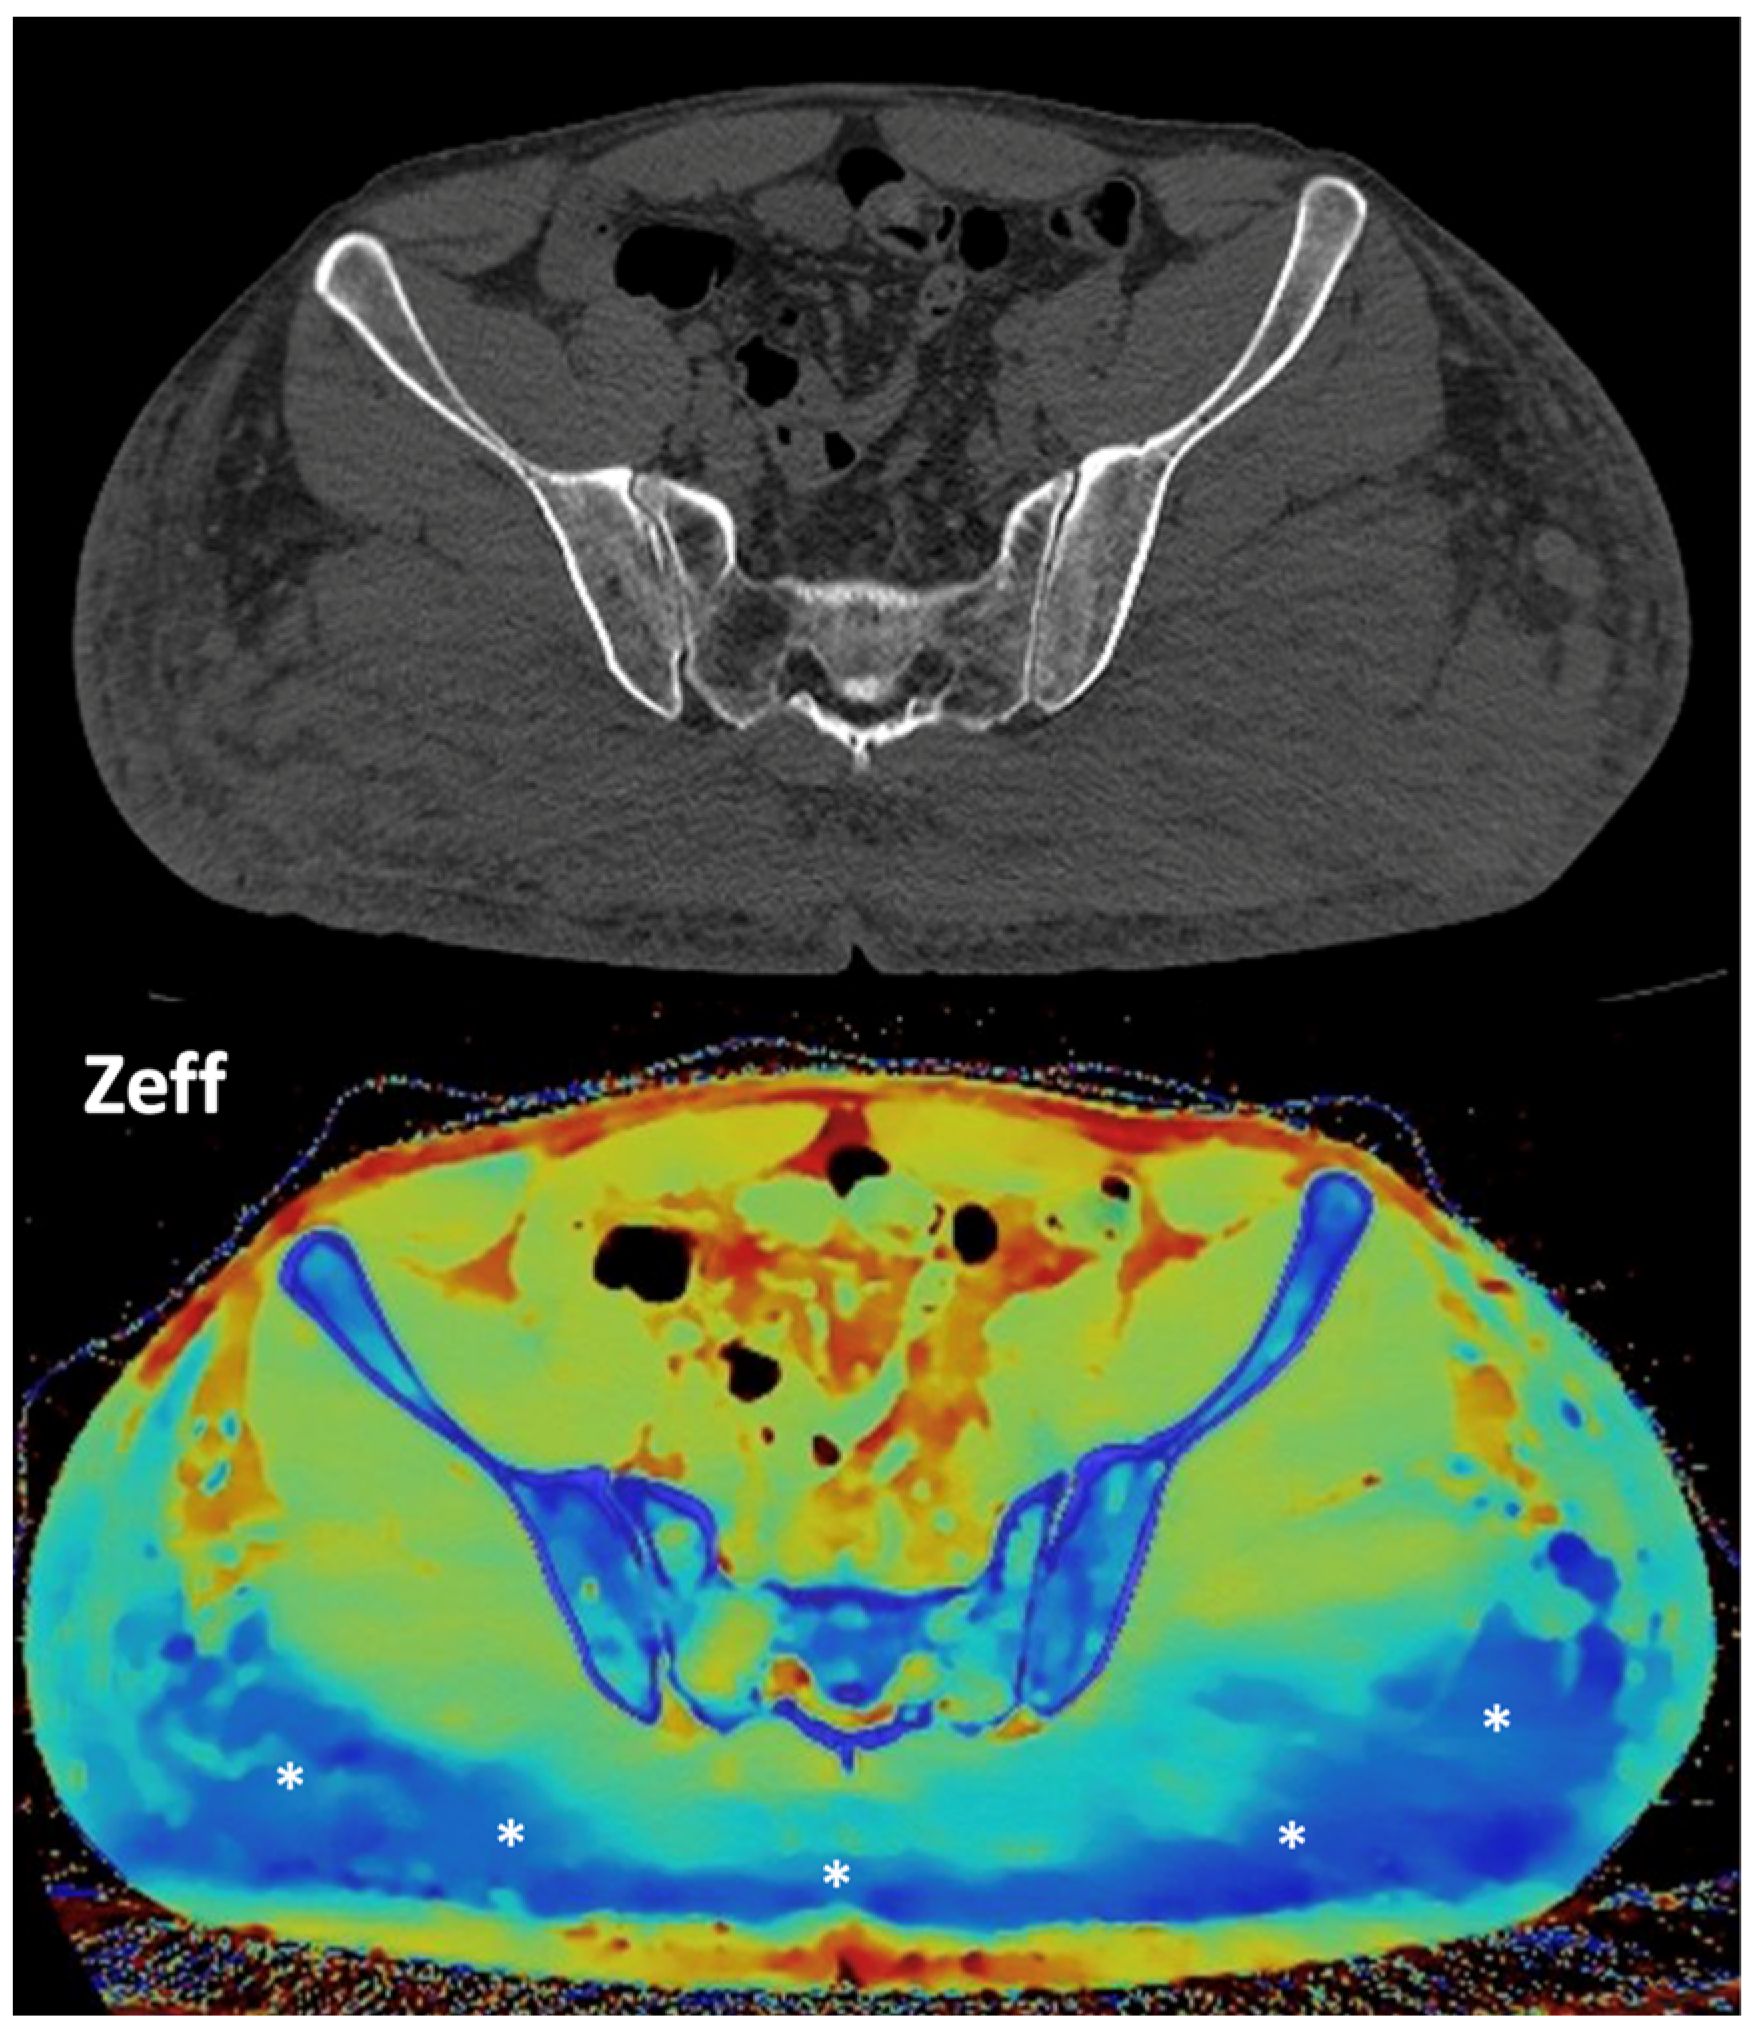

- Breast imaging. DECT seems to be a reliable tool for diagnosis and locoregional staging of breast cancer [36,37,38,39,40] (Figure 12). Klein et al. [37] found robust cut-off points for the differentiation of benign and malignant lesions (Zeff < 7.7, iodine content of <0.8 mg/mL). The DECT quantitative parameters may also be useful in predicting breast cancer invasiveness and histopathological and molecular subtypes of breast tumors. In the case of node staging, the similarity of quantitative DECT parameters between the primary lesion and axillary LNs may predict axillary metastasis in breast cancer [40,41].

- Zeff is also a quantitative index for characterization of the composition of a voxel, although determining a biological correlation of these changes to tumor microenvironment is challenging.